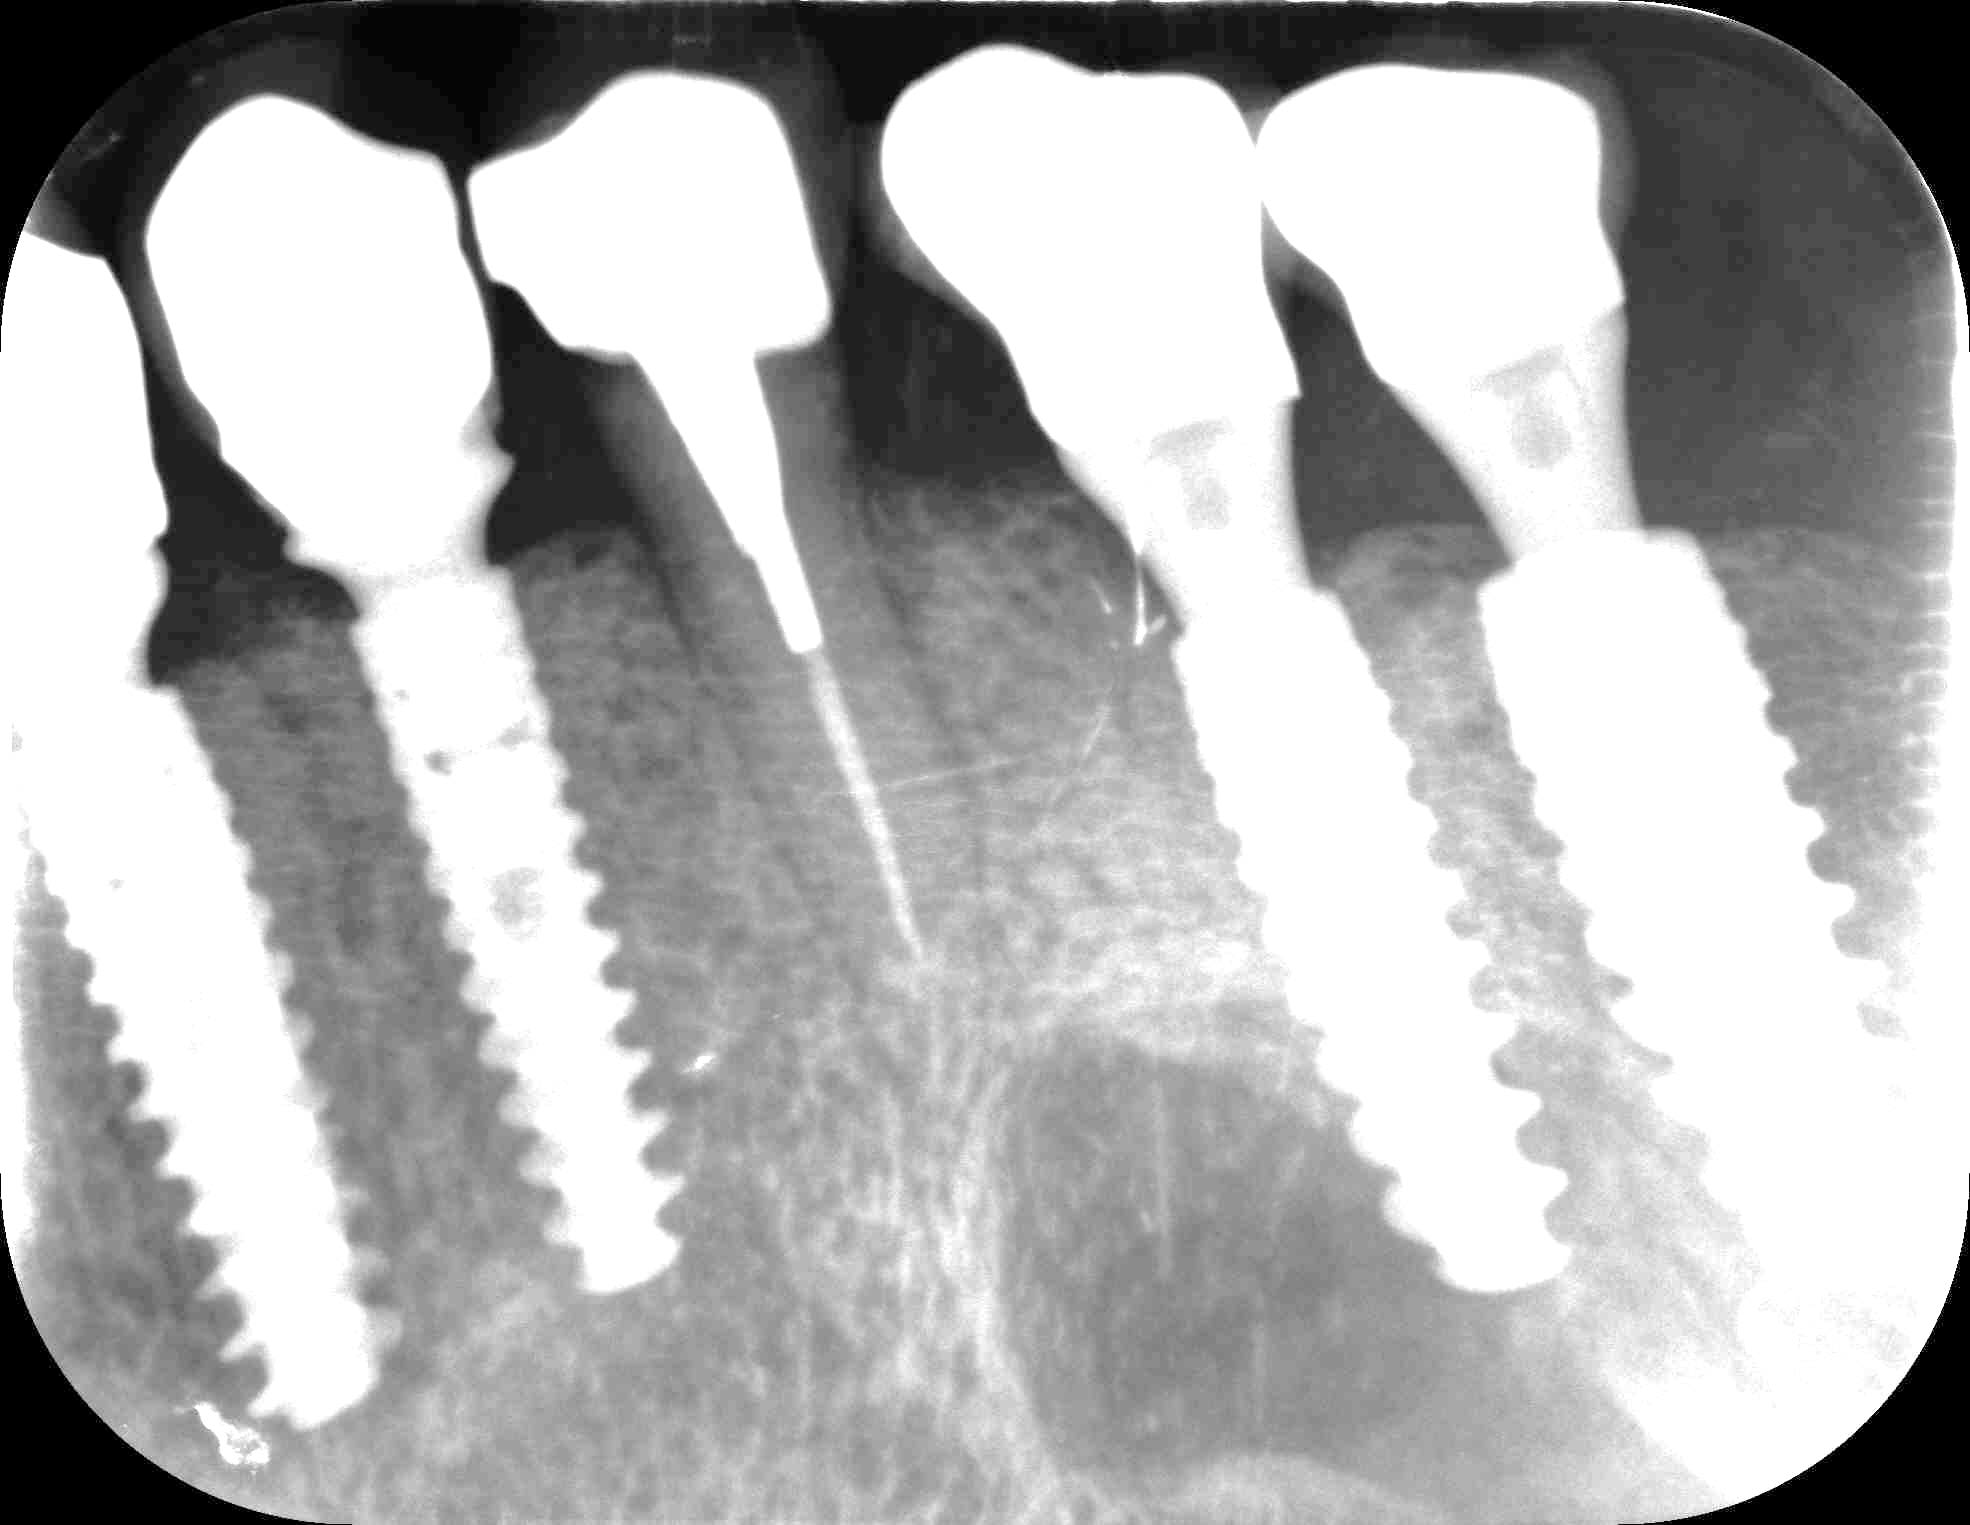

t as le la chance je viens d'avoir une urgence pour une 15 :

dérive mesiale des dents naturelles tu dis ?

Mmmmm ouaich ouaich

et donc , comment il a réussi a la visser cette couronne ( 36 ) ?

là , il y a perte de contact en distal .

déjà ça sent le pb occlusal

et si on regarde le secteur 40 , ç est la confirmation , a mon avis , ça , ç est un pb de décalage latéral qui a cassé la ceram .